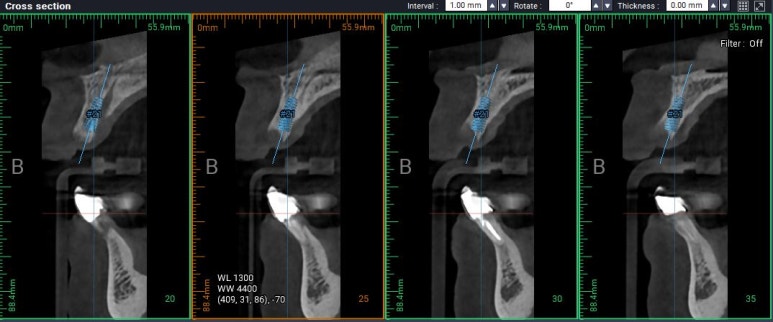

약 6주 뒤에 CT 촬영을 하였습니다.

위턱 앞니 부위에 남은 잇몸뼈가 거의 없었습니다.

가장 이해하기 쉬운 CT 자료입니다.

얼굴뼈의 아래 절반정도만 찍히는 치과용 CBCT를 사용하여 촬영 후 영상을 3D로 재건한 사진입니다.

보시다시피 앞니 네개가 제거는 되었지만, 정작 뼈는 가운데 부분만 말안장처럼 남아있어요.

가운데 남은 요 부위에 두개의 임플란트를 심어보기로 계획했어요.

그리고 양 옆에 비어있는 부분은 뼈이식을 무지하게 많이 해보기로 했습니다.

이런 식으로 가운데 남은 적은 양의 잇몸뼈 인에 임플란트 두개를 나란히 심기로 계획을 하였구요,

이건 위턱 오른쪽 가운데 앞니 부위 임플란트를 배열한 단면,

이건 위턱 왼쪽 가운데 앞니 부위 임플란트를 배열한 단면입니다.

axial view를 보시면, #12,22 부위에 정말로 엄청난 골소실이 있음을 보실 수 있을겁니다.

상악 전치부 보철은 양쪽 cantilever로 할 수 밖에 없는 상황이었습니다.

다행히도 남아있는 뼈의 양은 임플란트 두개를 담기에 딱 맞는 공간이었습니다.